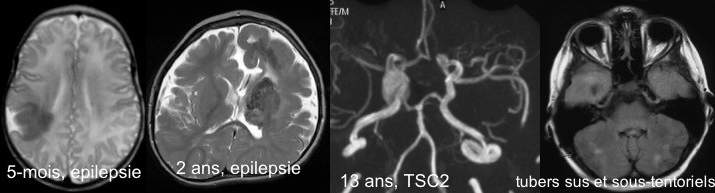

contrairement aux autres nodules ventriculaires de la sclérose tubéreuse ou tuberous sclerosis complex (TSC), ceux qui sont situés à proximité du foramen de Monro peuvent avoir une progression tumorale. cette progression tumorale est non linéaire (cf. ci-contre) et relativement imprévisible, elle est liée à la croissance et devient exceptionnelle à l’âge adulte.

- dysplasie corticale (tubers)

- nodules sous-épendymaires

- anévrisme (si mutation TSC2)

- polykystose rénale (si TSC2)